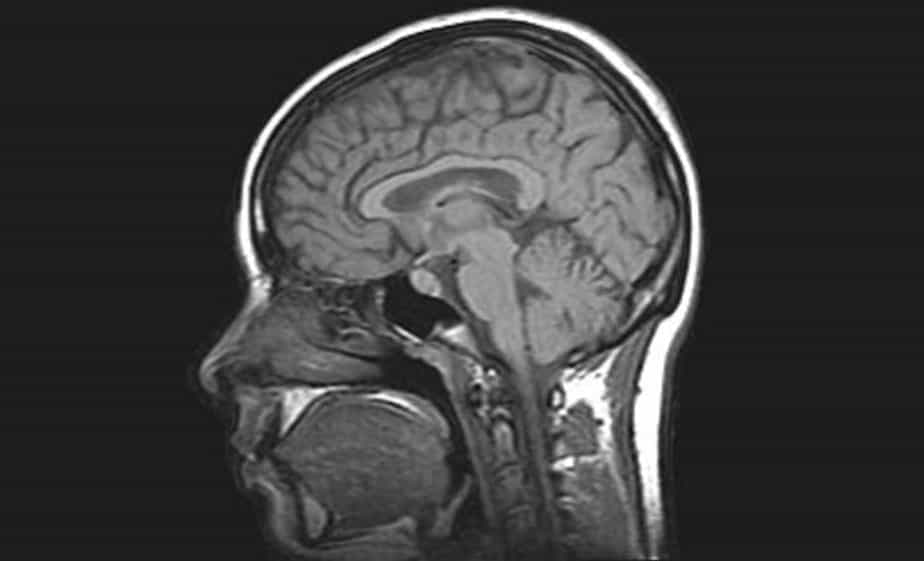

Brain MRI

Detailed examination with Brain MRI! Advanced MRI imaging and CT scanning services with expert radiologists. Check-up packages for early diagnosis! Medical imaging center.